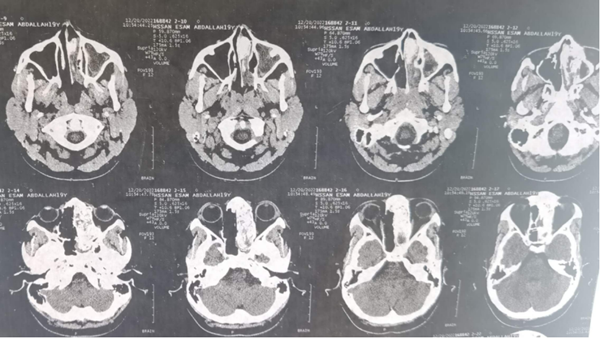

三周前的一个上午,援苏丹中国医疗队高天喜医生像平时一样按时上门诊开始诊疗工作,一个苏丹少年在家属陪同下走进诊室,咳嗽不止。陪诊家属代诉,患者15岁,间断咽痛,反复咳嗽5年。查体显示该患者双侧扁桃体重度肥大,左侧鼻腔巨大新生物,压迫鼻中隔偏至对侧鼻腔,双侧鼻腔无通气,张口呼吸。遂行血常规检查及鼻腔鼻窦CT检查,检查结果提示血常规无炎症表象,左侧鼻腔及巨大占位病变。

这名患者的症状及影像学检查显示鼻腔肿物大概率为良性,高天喜医生据此制定了治疗方案,术前予以口服抗生素一周,待控制炎症后全麻下一期行扁桃体及鼻腔鼻窦肿物切除术。被告知具体手术方案时,少年两眼放光,激动地伸出大拇指:“中国医生很好,能同时切除扁桃体及鼻腔肿物!”。后来助理据助理讲到,这名患者一度已经对治好鼻子不抱希望。